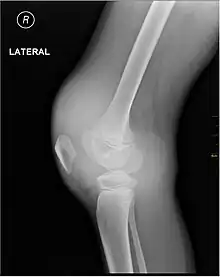

Lipohemarthrosis (blood and fat in the joint space) seen in a person with a subtle tibial plateau fracture. The arrow indicates a fluid level between the upper fat component and the lower blood component.